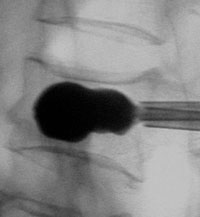

Для проведения хирургического вмешательства пациента располагают на операционном столе в положении на животе, спиной кверху. Пациент внутривенно получает седативные и обезболивающие медикаментозные препараты, постоянно ведётся контроль над функцией жизненно-важных органов пациента. Операция выполняется под постоянным рентгенографическим контролем, что позволяет свести к минимуму вероятность травматического повреждения внутренних органов и нервных структур.

После проведения обработки операционного поля хирург вводит в тело сломанного позвонка тонкую металлическую трубку-проводник (троакар). Следующим этапом становится размещение в области перелом специального баллона, который впоследствии заполняется жидкостью, находящейся под давлением. Результатом этой манипуляции является восстановление геометрии сломанного позвонка и формирование внутри его тела полости. Далее баллон сдувают и извлекают, а образовавшуюся в результате полость заполняют густым костным цементом. Это вещество спустя несколько минут затвердевает, обеспечивая внутреннюю стабилизацию позвонка и уменьшая риск развития такого рода компрессионных переломов в будущем.